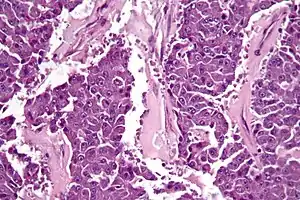

| Micrograph of an acinar cell carcinoma of the pancreas. H&E stain. | |

Histomorphologically, the tumour resembles the cells of the pancreatic acini and, typically, have moderate granular cytoplasm that stain with both PAS and PASD.[4]

Light microscopy of an acinar cell carcinoma biopsy typically shows granular appearance.[6] Immunohistochemistry is usually positive for trypsin, chymotrypsin and lipase.[6] On genetic testing, altered genes/proteins are typically found for p53, SMAD4, APC, ARID1A and GNAS.[6]